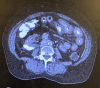

Ectopic varices account for 1%-5% of all variceal bleeding episodes. The most common presentation of cecal varices is an acute episode of a massive lower gastrointestinal hemorrhage. However, cecal varices can be found incidentally and can be silent for a prolonged period of time before presenting with a massive gastrointestinal hemorrhage. Through this case of a 63-year-old woman, we would like to highlight the paucity of literature in the treatment of nonbleeding cecal varices.